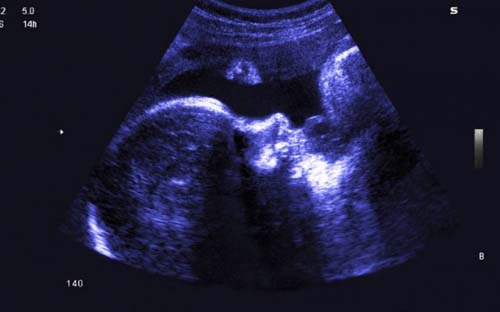

Ilustração